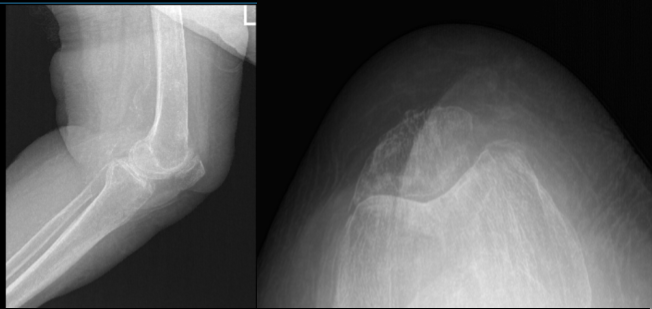

Xray were presented and reviewed, the patient’s femur was healed intertrochanteric fracture but there are mild osteoarthritic degenerative changes found on her knee. We discussed the possibility of etiology of knee pain and treatment options.

Left Knee X-ray Complete with Patella